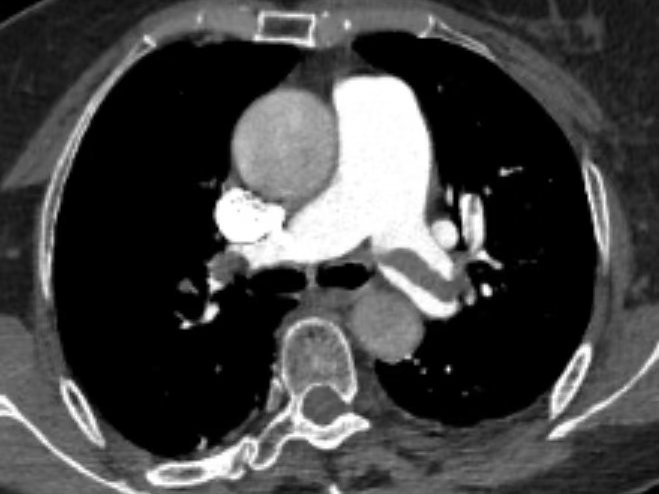

9月14凌晨2点,70岁的张女士上卫生间时突然晕厥,随后感胸闷、气喘,医疗团队反应迅速,行心电监测提示血氧饱和度70%!血压77/40mmHg,心率105次/分,结合患者症状及体征,考虑是发生了肺栓塞。在重症医学科团队协助下,为患者行呼吸机辅助通气,在呼吸机的维持下急查肺动脉CTPA检查结果显示:双肺动脉及其分支广泛肺动脉栓塞,肺动脉高压征象;心脏标志物增高;生命体征极不平稳,生命危在旦夕。